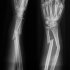

骨折部に注射してたった3分で固定可能! 中国で革命的な接着剤が開発され大注目